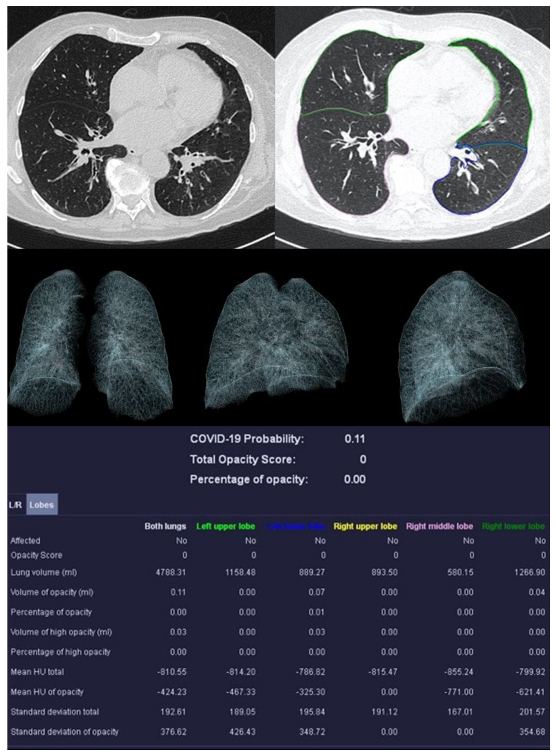

3.2. Image Analysis

| Mean COVID-19 Probability ± SD | 0.80 ± 0.36 | 0.33 ± 0.4 | 0.55 ± 0.47 | 0.66 ± 0.44 |

| Mean LSS ± SD | 8 ± 5 | 5 ± 4 | 5 ± 6 | 0 ± 0 |

| Mean PO ± SD in % | 26.39 ± 23.22 | 12.52 ± 17.97 | 18.90 ± 26.27 | 0.05 ± 0.12 |

| Mean PHO ± SD in % | 6.42 ± 7.68 | 3.60 ± 4.47 | 5.86 ± 10.04 | 0.01 ± 0.02 |